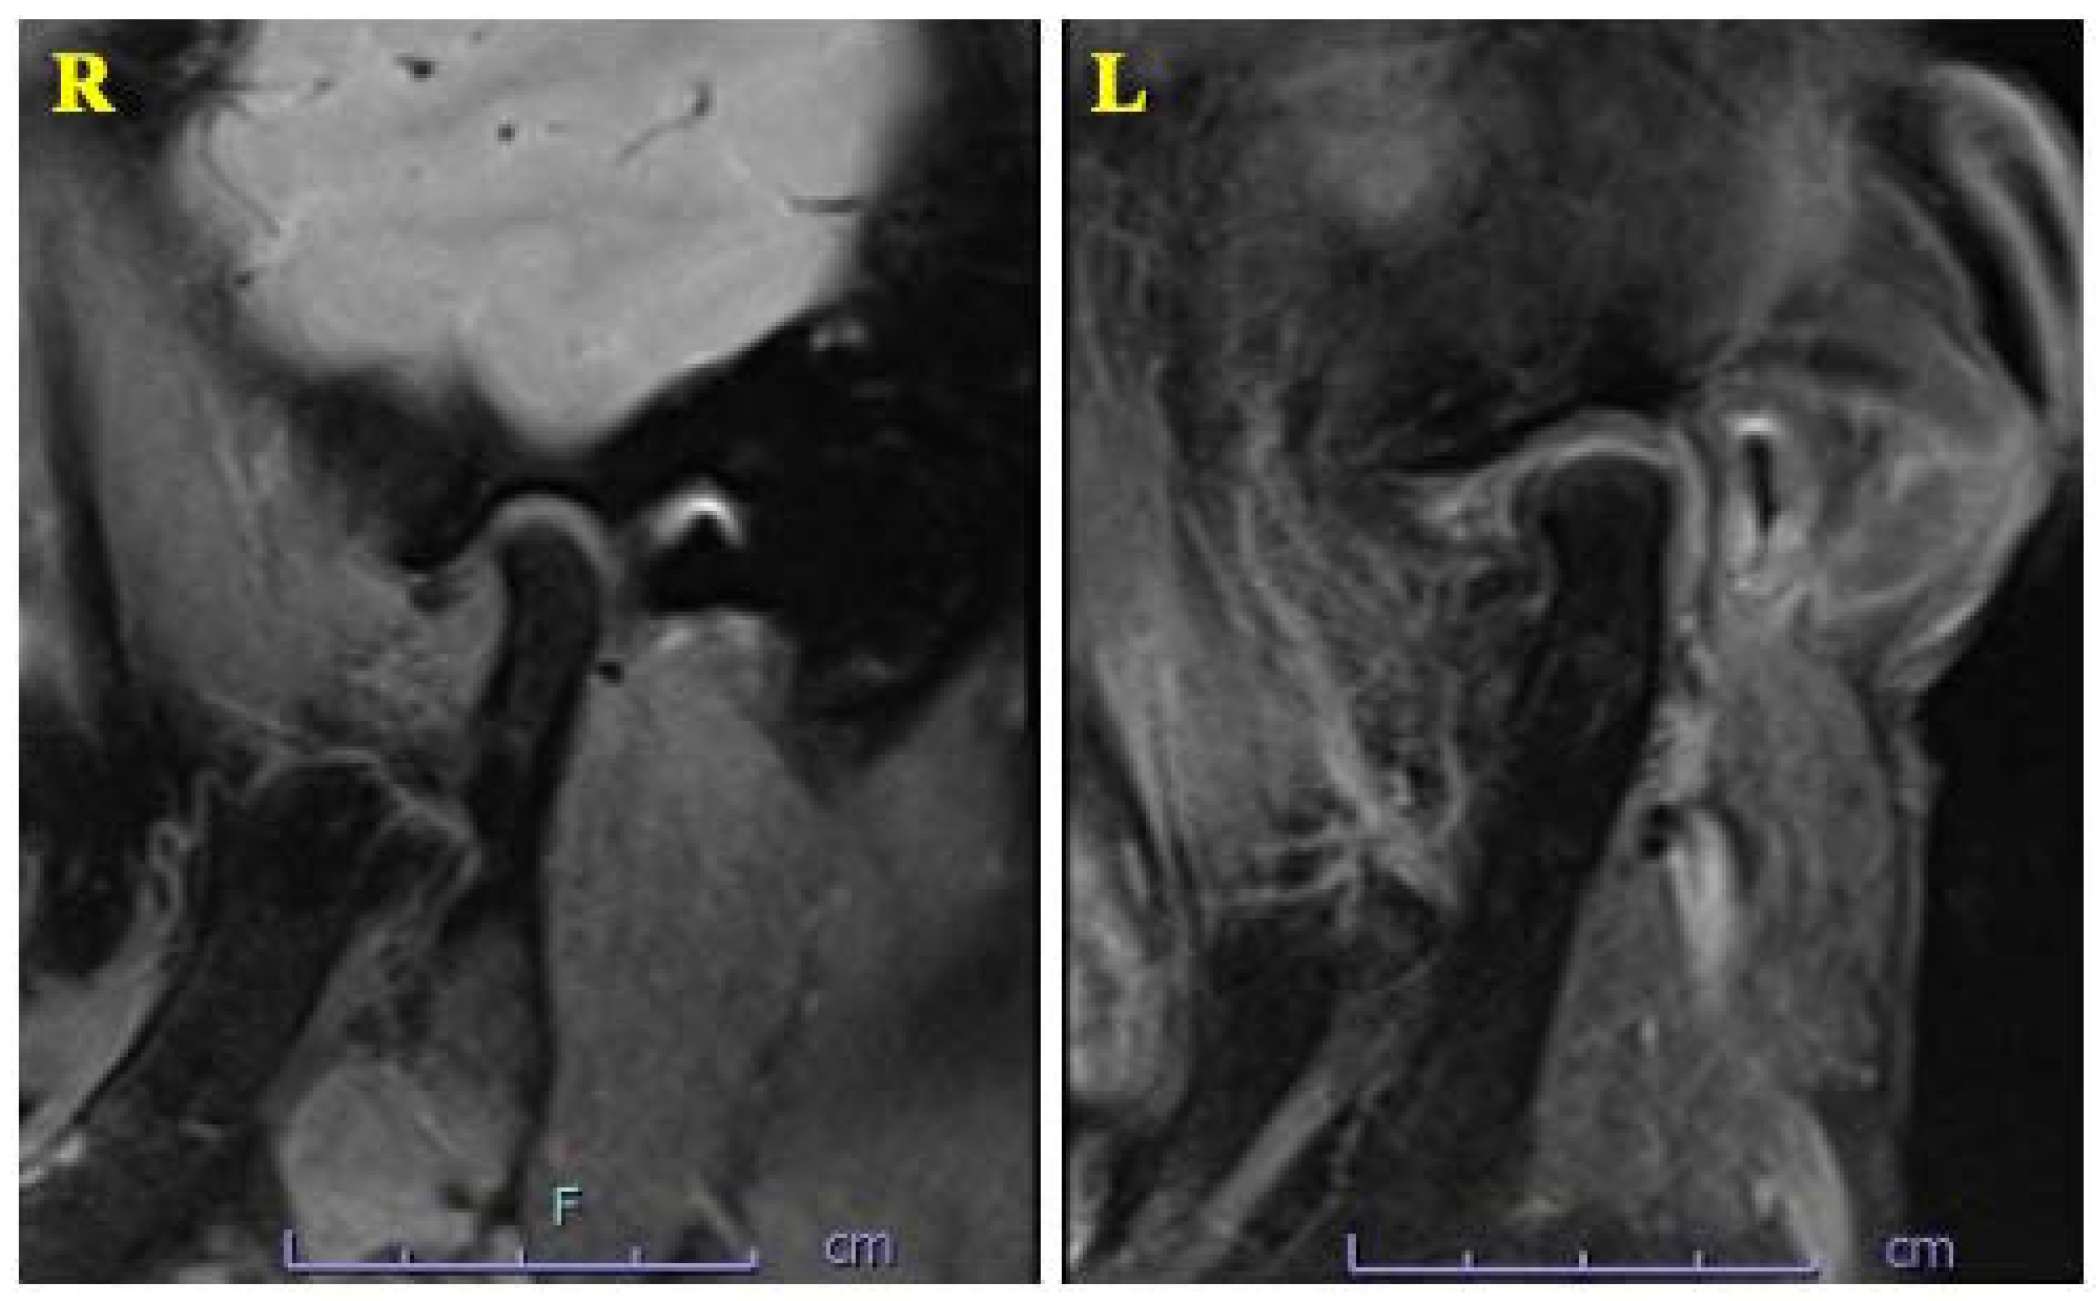

2. Case Presentation